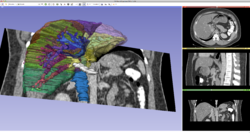

Slicer4DTI Tutorial.png

Slicer4 Neurosurgical Planning Tutorial

• The Neurosurgical Planning tutorial course guides end-users through the generation of fiber tracts in the vicinity of a tumor.

• Author: Sonia Pujol, Ph.D., Ron Kikinis, M.D.

• Audience: Clinicians and Clinical Researchers

• Modules: Segment Editor, Tractography

• Based on 3D Slicer version 4.10

• The White Matter Exploration dataset contains a Diffusion Weighted Imaging scan of a brain tumor patient.

NeurosurgicalPlanningTutorial.png